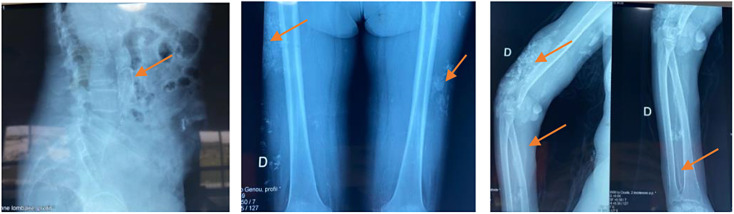

Case presentation: We present the case of a 60-year-old woman, with a history of renal lithiasis, hypertension, and end-stage renal disease on hemodialysis complicated by hyperparathyroidism and aortic valve replacement. She developed extensive necrotic lesions on both lower limbs and upper extremities, prompting a diagnosis of calciphylaxis. Radiographic and biopsy findings supported the diagnosis, revealing characteristic calcifications. Treatment involved antibiotics, oral thiosulfate, daily hemodialysis, hyperbaric oxygen therapy, and discontinuation of calcium and alfacalcidol, with alendronate initiation. Unfortunately, despite these interventions, the patient experienced a rapid clinical decline, developing septic shock necessitating bilateral leg amputations. Regrettably, she succumbed to the disease 10 days later.